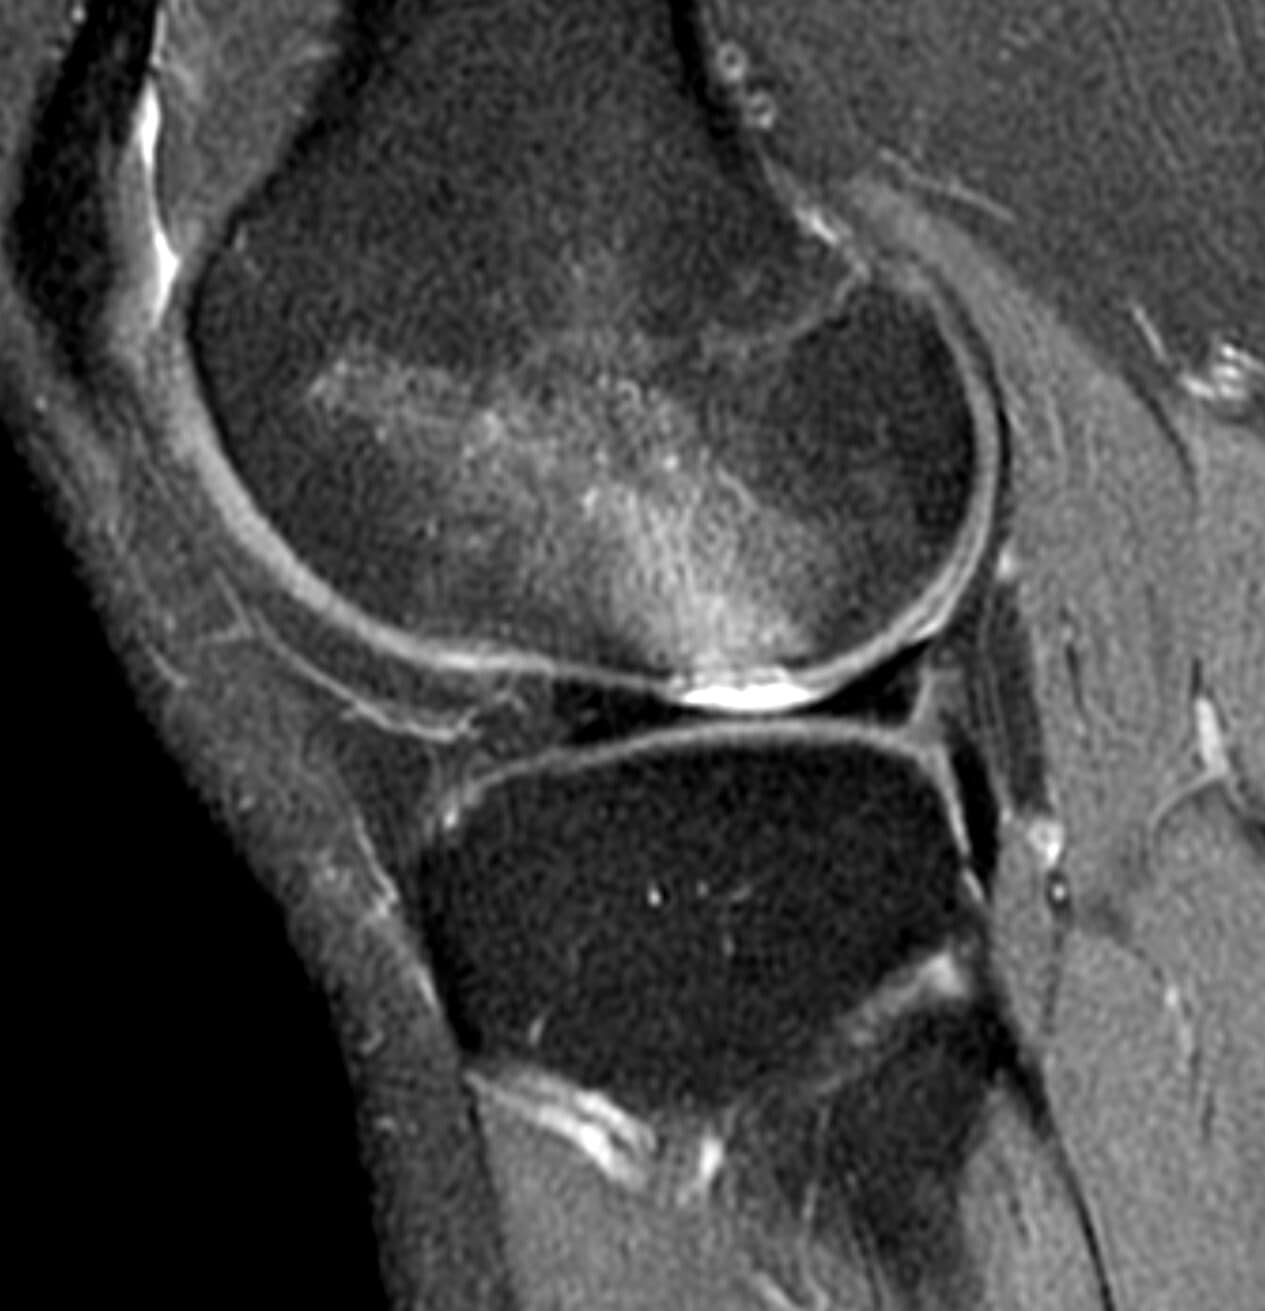

Pre-Op MRI